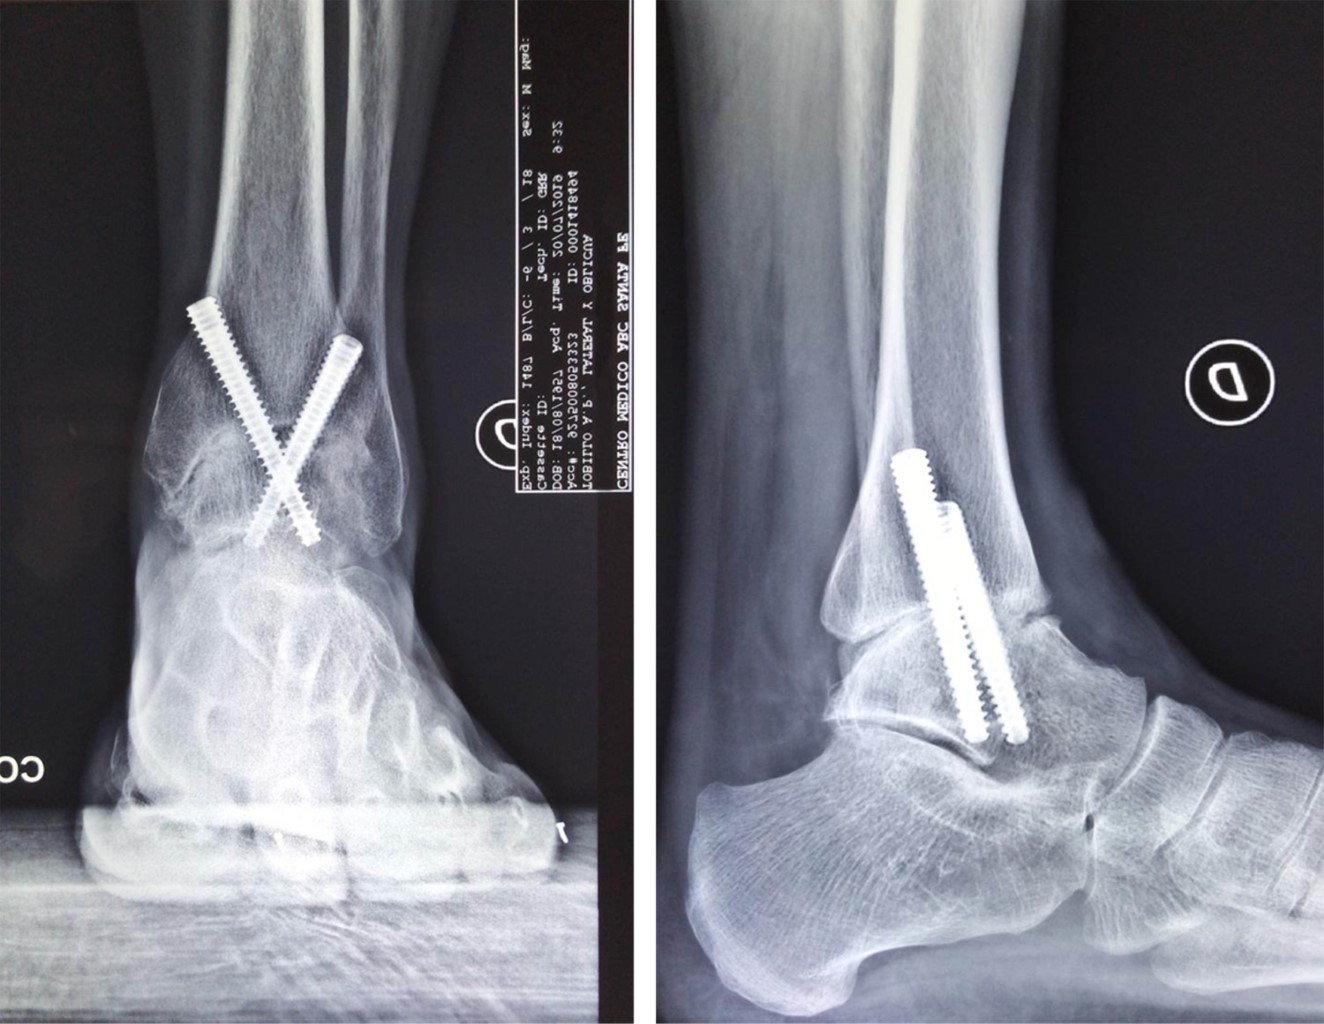

Paciente del sexo femenino de 56 años de edad, con antecedente de artrodesis de tobillo de 22 años de evolución. Presentó dolor, dificultad para la marcha, deformidad en equino del pie no reductible pasivamente, varo del retropié y recurvatum compensatorio de la rodilla (Figura 1).

El examen radiográfico mostró una consolidación completa de la artrodesis del tobillo y en neutro en los planos sagital y coronal, así como osteofito dorsal de la articulación talo-navicular y apertura anormal de la articulación sub-talar en la proyección sagital. En la vista anteroposterior se evidenció aducto del antepié a expensas de la articulación talo-navicular y cambios artrósicos incipientes (Figura 2).

Con estos hallazgos clínico-radiográficos se decidió realizar la conversión de la artrodesis tibio-talar a un reemplazo total de tobillo.

Figura 1

Figura 2